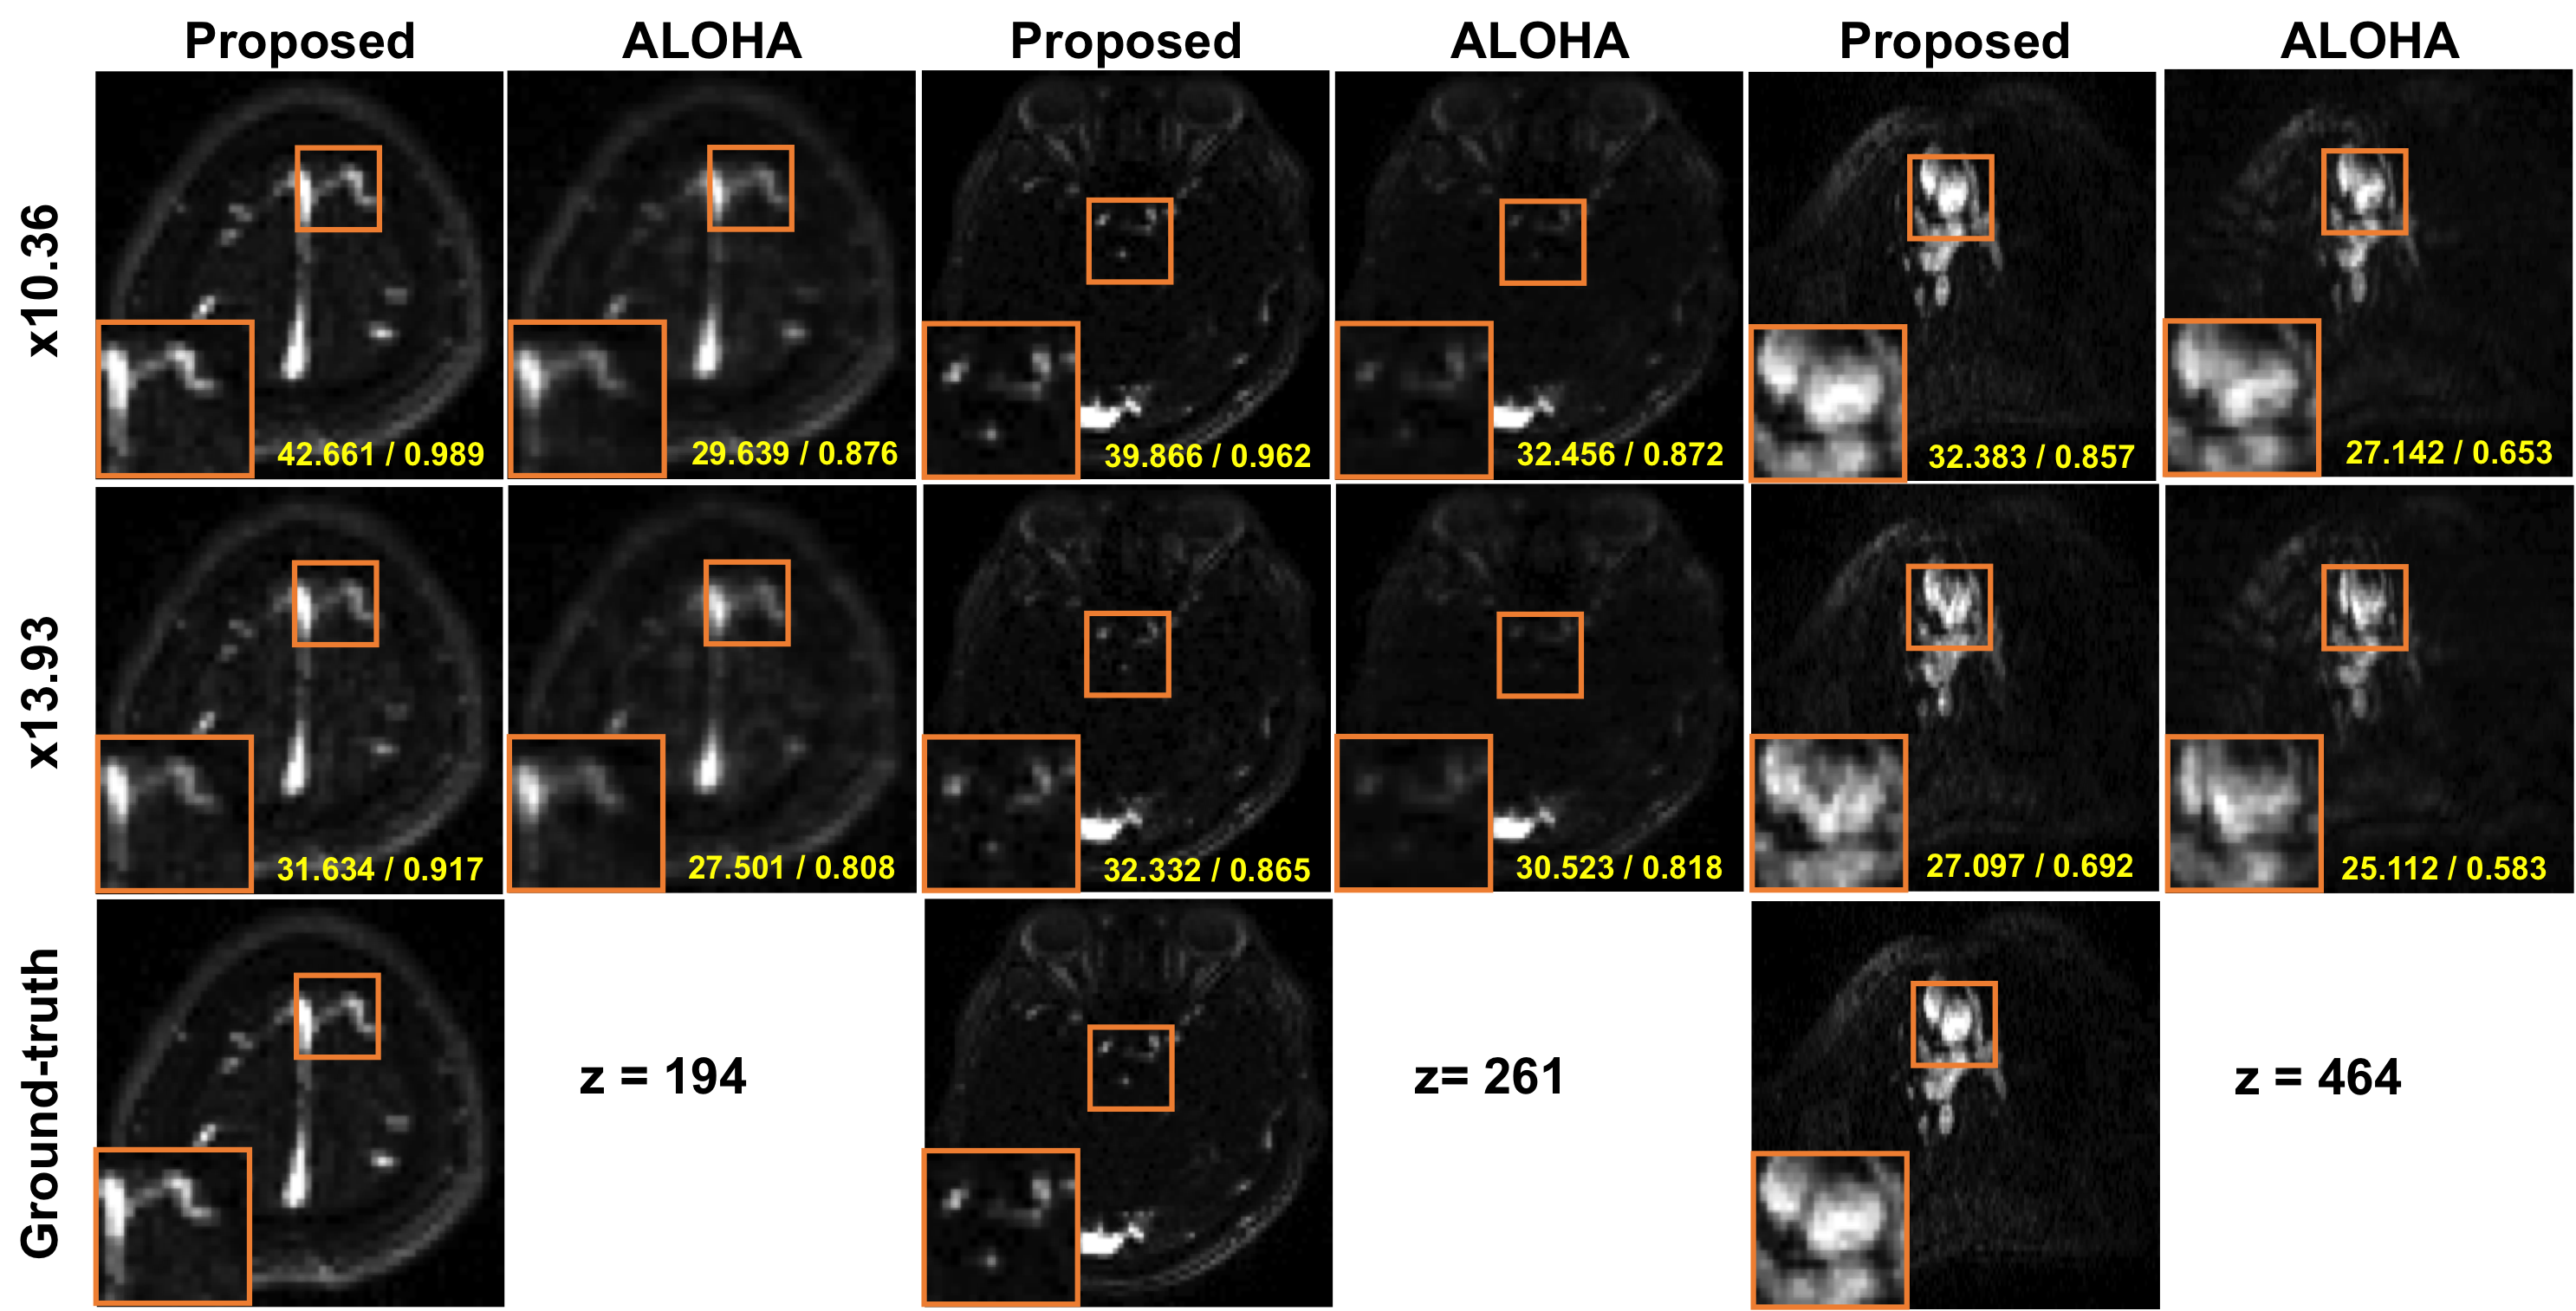

We first compare the performance of the proposed -space deep learning for parallel MR image reconstruction. In this experiments, the fully sampled -space data generated using GRAPPA were considered as the ground-truth, from which retrospective sub-sampling were performed at various downsampling ratios, which corresponds to specific view sharing number (VS). Then, the proposed multi-coil -space deep learning and ALOHA method were applied for comparative studies. The axial reconstruction results and the coronal reformatted images in Fig.ย 6 clearly show that the proposed method significantly outperformed ALOHA. For example, near perfect reconstructions are obtained at downsampling (i.e. VS=3) using the proposed method, while still blurry images are observed from the ALOHA reconstruction. In terms of PSNR and SSIM values, the proposed method significantly outperforms the ALOHA. For example, from the axial reconstruction images, at acceleration factor (i.e. VS=2), the proposed -space deep learning is about dB better than ALOHA in terms of PSNR, whereas at downsampling (i.e. VS=3), the proposed -space deep learning is about dB better than ALOHA. When we compare the results in coronal reformatted images, similar PSNR gains were observed. At acceleration factor, the proposed -space deep learning is about dB better than ALOHA in terms of PSNR, whereas at , the proposed -space deep learning is about dB better than ALOHA.